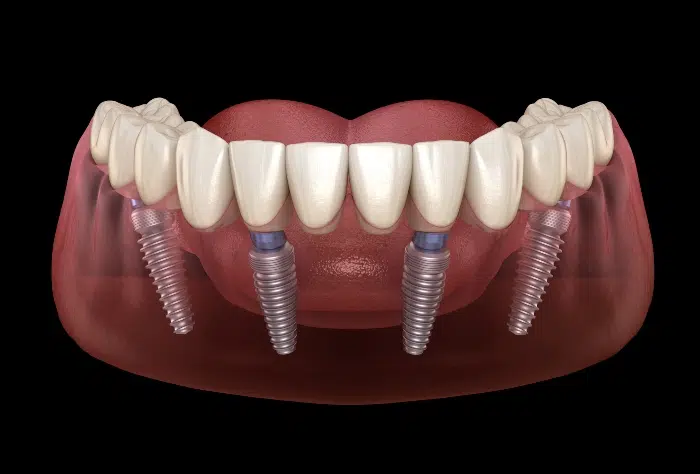

All on X implant systems include All on 4, All on 6 and All on 8 implant systems, which differ in how many screws are used per bridge. They are the best choice for patients who want to have the most affordable and very durable implant system for restoring many teeth at once. Patients who have more dense jaws and desire even better stability can choose All on 6 systems. More information about our All on X implant procedures, including All on 4 dental implants.

All on 4 implant systems have four screws per bridge and are among the most popular options at our clinic. Their cost is the lowest among all All on X systems.